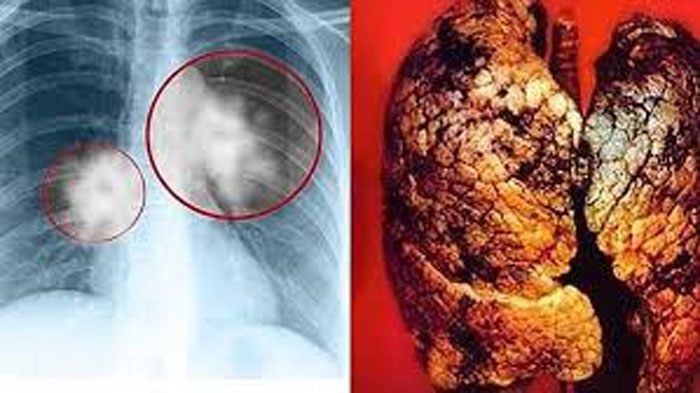

Nhiều người thường bỏ qua những dấu hiệu đầu tiên của ung thư phổi

Ung thư phổi thường khởi phát bằng các triệu chứng dễ nhầm lẫn với bệnh đường hô hấp thông thường nhưng nhiều người không chú ý.

Bác sĩ cảnh báo: Dấu hiệu sớm của ung thư phổi không phải đau ngực, mà là 5 triệu chứng bất thường này, nhiều người bỏ qua

Nghiên cứu y học cho thấy, 70% bệnh nhân ung thư phổi phát hiện bệnh ở giai đoạn muộn do nhầm lẫn triệu chứng sớm với các bệnh hô hấp thông thường.